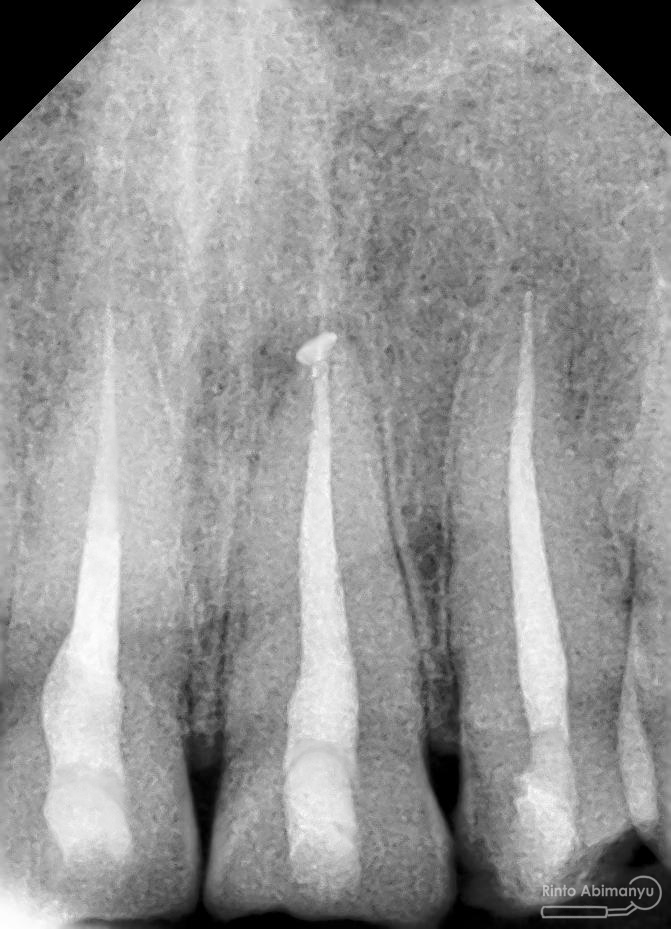

Foto radiografis gigi 11 21 22 yang mengalami fraktur

Dari pemeriksaan radiografis lokasi fraktur menyerempet kamar pulpa pada ketiga gigi tersebut… Saya sampaikan kepada pasien bahwa ketiga gigi tersebut memerlukan perawatan saluran akar terlebih dahulu baru kemudian dilanjutkan dengan restorasi indirek… kenapa saya pilih restorasi indirek? Pertimbangannya adalah sisa struktur mahkota gigi yang ada bila hanya di “sambung” dengan restorasi direk dalam jangka panjang rentan mengalami kerusakan, yang kedua pemilihan warna akan lebih maksimal pada kasus ini…. Pasien setuju dengan rencan perawatan yang saya jelaskan…